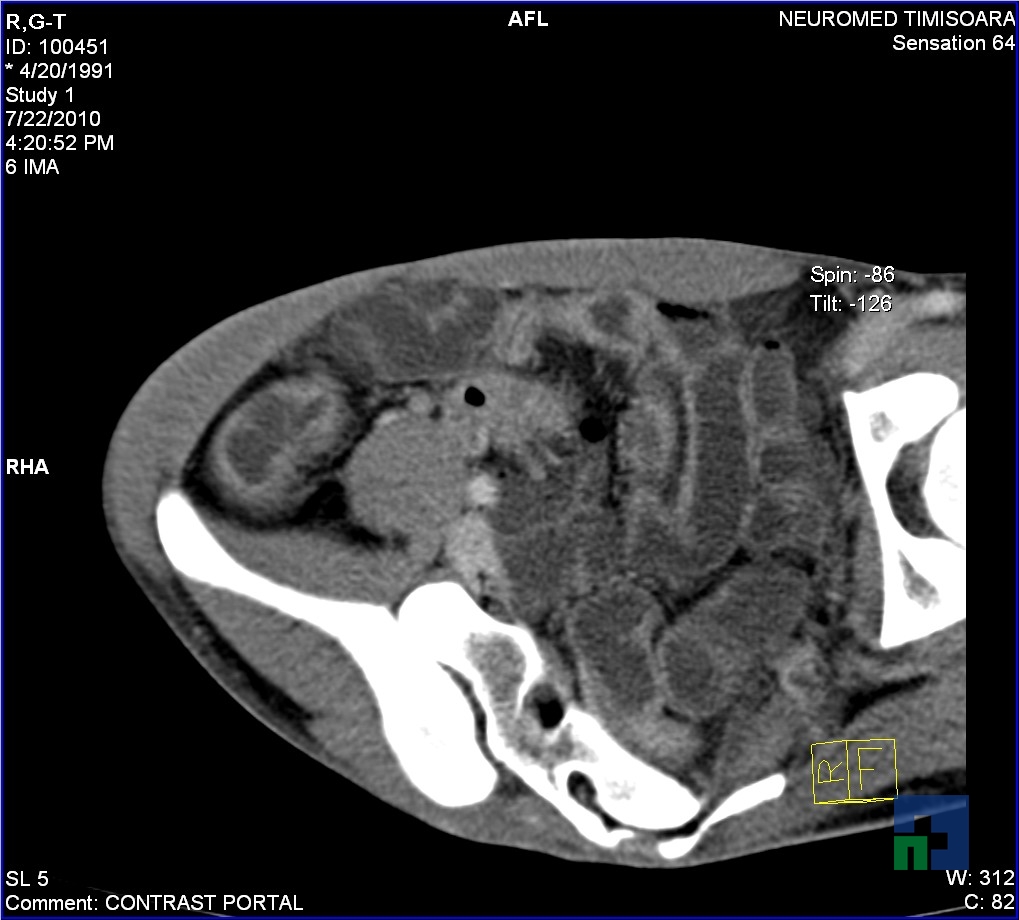

- Diagnosticul edemului cerebral, a contuziei cerebrale, a leziunilor axonale difuze edematoase/hemoragice, a dilacerării cerebrale, a hematomului intraparenchimatos posttraumatic, a hematoamelor subdurale/extradurale (acute, subacute, cronice), a hemoragiei intraventriculare, a hemoragiei subarahnoidiene